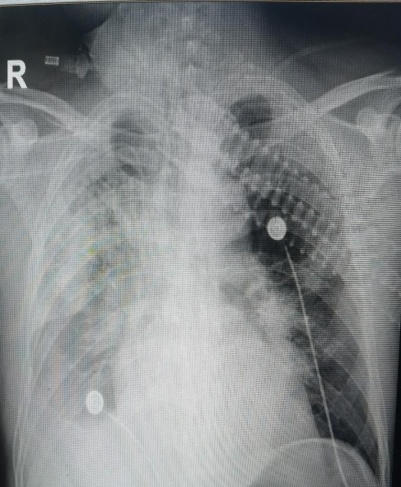

ECMO上機(jī)前全身花斑,肺部大面積病灶 “生死時(shí)速”啟動(dòng)ECMO治療 1月6日,在感染重癥醫(yī)學(xué)科陳佳主任的主持下,組織感染科、呼吸科、外科、影像科、輸血科等專家開展多學(xué)科聯(lián)合會(huì)診,在結(jié)合感染科、結(jié)核科專家給予的個(gè)體化治療方案的基礎(chǔ)上,最終確定了使用ECMO輔助治療。陳佳主任帶領(lǐng)感染重癥醫(yī)學(xué)科團(tuán)隊(duì)立即對(duì)患者進(jìn)行VV-ECMO治療,迅速為患者建立ECMO通路,在ECMO的輔助下,患者全身氧合得到改善,循環(huán)逐漸穩(wěn)定,搶救取得階段性勝利。 然而,與其他ECMO治療的患者相比,該患者系艾滋病合并重癥肺結(jié)核,免疫功能有重大缺陷,ECMO運(yùn)行期間隨時(shí)可能發(fā)生的出血或血栓風(fēng)險(xiǎn)、繼發(fā)新感染,抗結(jié)核藥物對(duì)肝腎功能血液系統(tǒng)影響,且職業(yè)暴露風(fēng)險(xiǎn)較大,任何并發(fā)癥的發(fā)生,任何細(xì)節(jié)的疏忽都可能危及患者生命。如何進(jìn)行抗凝監(jiān)測(cè)、院感防控、避免職業(yè)暴露,如何在最短的時(shí)間內(nèi)幫助患者恢復(fù)受損的肺功能,盡早撤機(jī)成了感染重癥醫(yī)學(xué)團(tuán)隊(duì)面臨的最大挑戰(zhàn)。 ECMO通路建立,成功上機(jī) 24小時(shí)的精準(zhǔn)監(jiān)護(hù),合力攻堅(jiān)432小時(shí) 醫(yī)療團(tuán)隊(duì)在做好ECMO系統(tǒng)日常維護(hù)的同時(shí),還要”盯牢”患者各項(xiàng)生命體征的變化,不放過(guò)任何細(xì)節(jié)處理。在ECMO運(yùn)行的432個(gè)小時(shí)里,緊密合作,合力攻堅(jiān),對(duì)患者的呼吸、循環(huán)、臟器功能等多個(gè)方面進(jìn)行精細(xì)化管理與治療。 ECMO系列聯(lián)合治療 最終,在全體醫(yī)護(hù)人員的共同努力、多學(xué)科協(xié)同救治下,患者的病情得到控制,肺部病灶吸收好轉(zhuǎn),于1月24日成功撤離ECMO。目前患者生命征平穩(wěn),繼續(xù)接受后續(xù)治療中。這次成功的救治,不僅挽救了患者生命,也實(shí)現(xiàn)了我院ECMO技術(shù)上突破,這是貴州省首例艾滋病合并重癥肺結(jié)核患者的ECMO治療,標(biāo)志著貴州省貴陽(yáng)市公共衛(wèi)生救治中心在傳染危重癥患者救治領(lǐng)域取得了新突破。為ECMO支持下感染危重癥患者轉(zhuǎn)運(yùn)奠定了技術(shù)基礎(chǔ),為免疫缺陷患者的救治積累了寶貴的經(jīng)驗(yàn)。 ECMO支持后循環(huán)穩(wěn)定,花斑逐漸改善 貴陽(yáng)市公共衛(wèi)生救治中心作為貴州省感染專科聯(lián)盟牽頭單位,將在感染危重癥患者的救治領(lǐng)域繼續(xù)勇攀高峰,持續(xù)提升醫(yī)療服務(wù)能力和水平,守護(hù)患者生命健康。